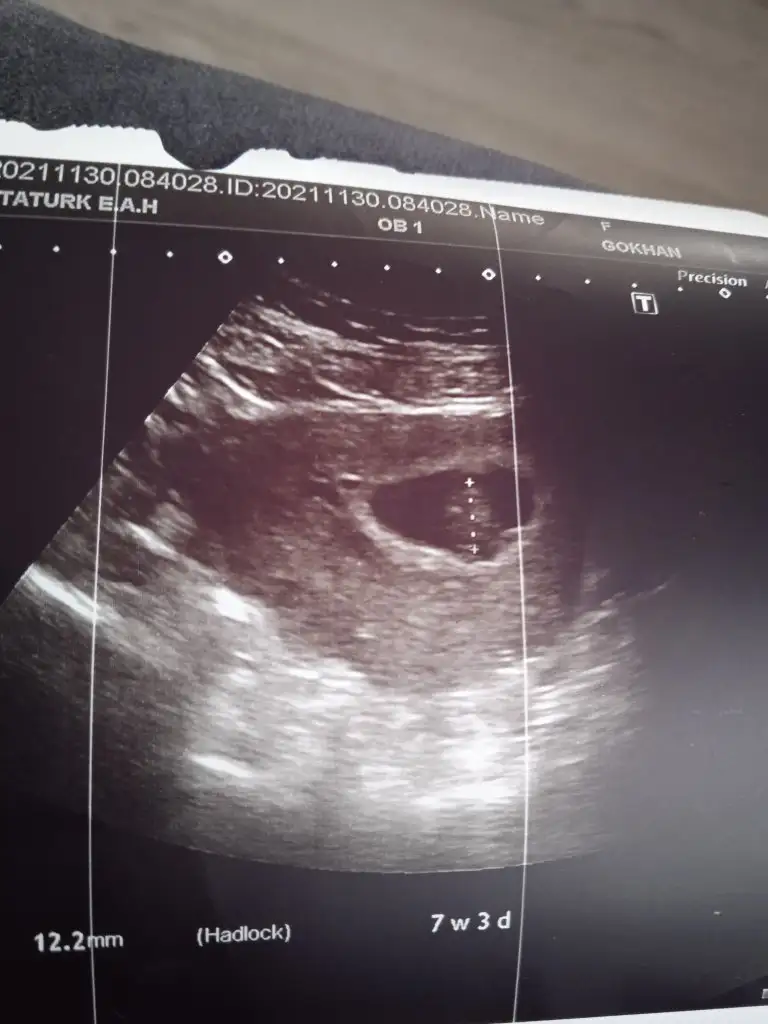

prenses gibi7+3 karindan usg

Tutuyormu diye merk etmistim aslinda daha once ucretle bakan birine de sormustum o da kiz demisti ama doktorlar erkek diyor herseyimizi isimli sekilde erkeğe göre hazirladik bir surpriz olmaz umarimprenses gibi![]()

doktor ne dediyse odurTutuyormu diye merk etmistim aslinda daha once ucretle bakan birine de sormustum o da kiz demisti ama doktorlar erkek diyor herseyimizi isimli sekilde erkeğe göre hazirladik bir surpriz olmaz umarimpipisini de gormustuk ama